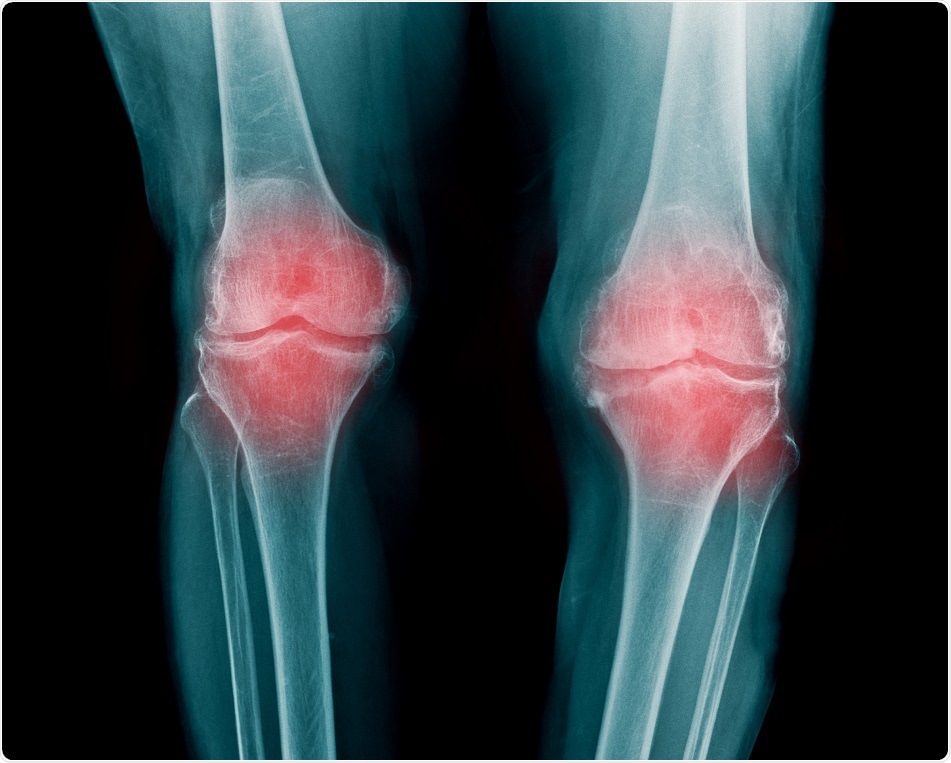

Xương khớp đầu gối là nơi dễ bị viêm nơi người mập. (Shutterstock.com)

Một nghiên cứu MRI mới được trình bày trong tháng 11 vừa qua, tại cuộc họp hàng năm của Hiệp Hội X Quang Học Bắc Mỹ (RSNA) cho biết những người béo phì giảm trọng lượng cơ thể chỉ bằng cách tập luyện, hoặc chỉ bằng cách ăn kiêng, đều không tốt cho xương khớp đầu gối.

Theo Trung Tâm Kiểm Soát và Phòng Ngừa Bệnh Tật Hoa Kỳ, mập hay béo được coi là nguyên nhân gốc rễ của viêm khớp mãn tính, một căn bệnh mạn tính thường ảnh hưởng ở người lớn trên 60 tuổi. Viêm xương khớp phổ biến nhất ảnh hưởng đến xương khớp đầu gối, và trong nhiều trường hợp, có thể phải thay khớp gối thì tình trạng trở nên tệ hại hơn.

Điều rất quan trọng đối với những người có dấu hiệu sớm bị viêm xương khớp, hoặc những người có nguy cơ phát triển bệnh, là phải làm chậm sự thoái hóa khớp. Nhưng. để làm chậm thoái hóa khớp, nhưng giảm cân chỉ bằng tập luyện mà không bồi bổ thức ăn, hoặc chỉ kiêng ăn mà không tập luyện đều không đem lại kết quả tốt.

Nhóm giảm được cân nặng cũng chia ra, một nhóm tập luyện, và ăn kiêng. Nhóm còn lại chỉ tập thể dục, hoặc chỉ ăn kiêng. Kết quả cho thấy nhóm người áp dụng phác đồ giảm cân bằng cách tập luyện và ăn kiêng có xương khớp đầu gối cải thiện hơn nhiều so với người chỉ thực hiện một trong hai cách giảm cân là tập luyện hoặc ăn kiêng.